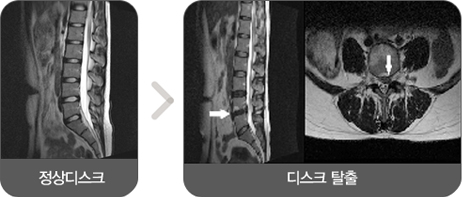

허리디스크는 무거운 것을 들어 올리거나 교통사고, 물리적 충격에 의해 디스크가 본래의 자리에서 밀려나와 신경을 눌렀을 때 통증이 발생하는 질환입니다.

일반적으로 신경이 눌려서 발생하고 허리와 하반신(허벅지, 종아리, 발 등)의 통증을 동반합니다.

※ 디스크 : 척추뼈와 뼈 사이에 있는 물렁뼈 조직의 구조물